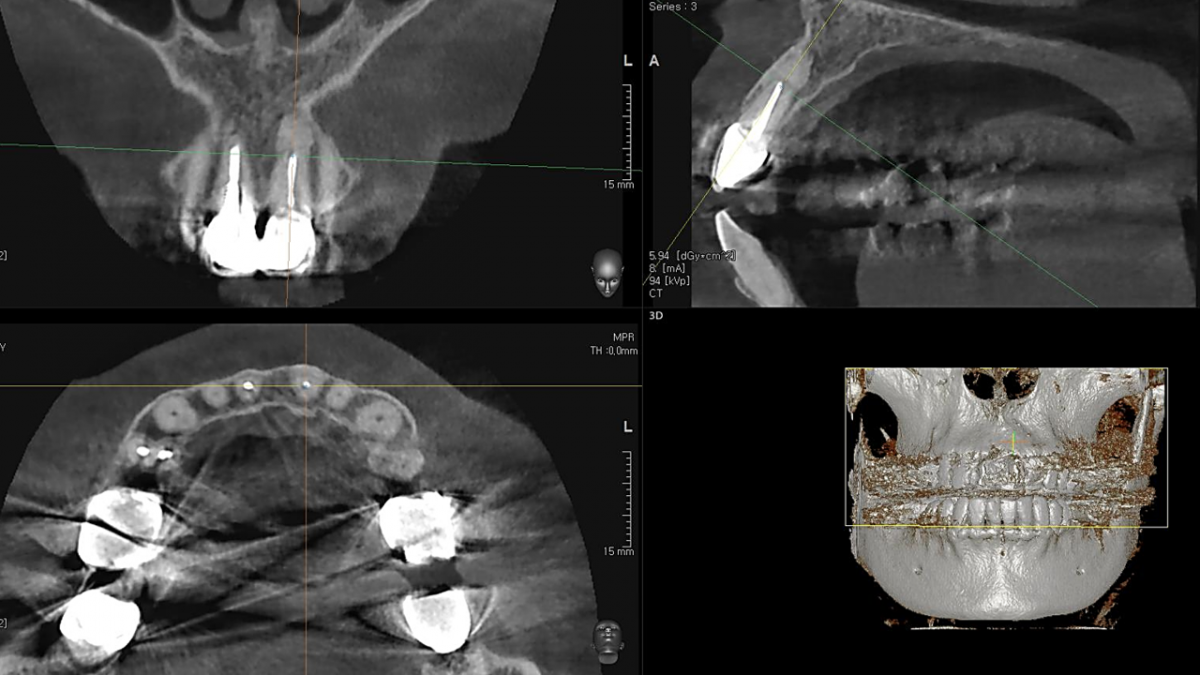

Apicorctomy /central incisor /GBR ; 6-year follow up.

<CJ SBN> Apicorctomy /central incisor /GBR ; 6-year follow up.

▲CBCT. Left central incisor had a apical lesion.